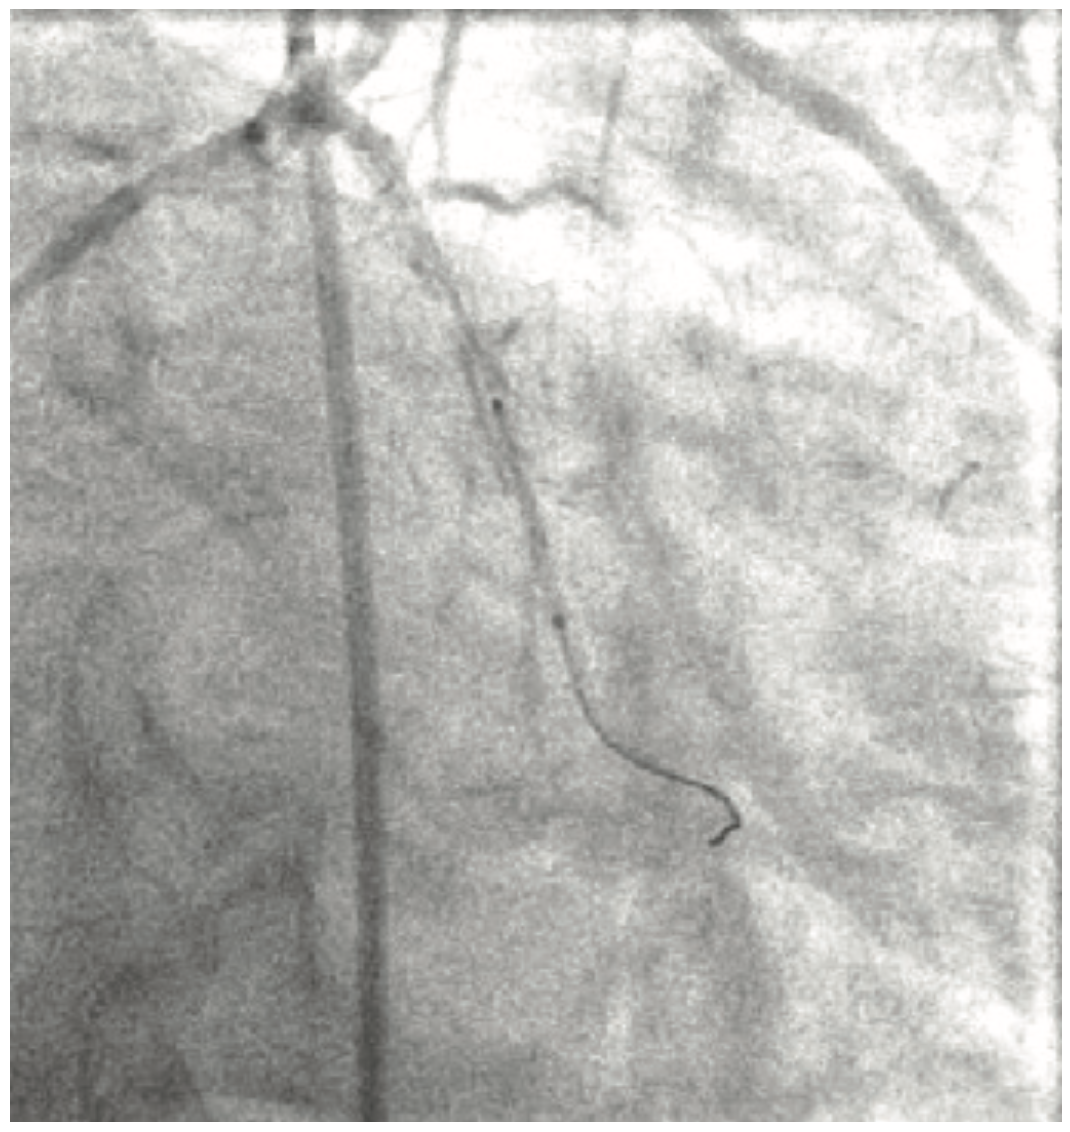

Figure 4 and Video 2A and Video 2B show the LCx in antero-posterior (AP) caudal and right anterior oblique (RAO) caudal projections. Due to the cumulative 290° angle between the takeoff of the proximal LM segment and the direction of the LCx artery, it was not possible to advance a wire past the proximal LCx artery segment. Four different wires were used (Sion Blue [Asahi Intecc], Whisper extra support [ES] [Abbott Vascular], Choice Extra Support [Boston Scientific], and Whisper medium support [MS] [Abbott Vascular]) without successfully passing beyond the proximal LCx segment, due to recurrent wire prolapse back into the ramus branch once the wires made the turn into the mid LCx segment. The friction caused by the LCx angulation eliminated the transmission of torque to the tip of the wire despite the use of polymer-jacketed and hydrophilic wires (Figure 5 and Video 3). We did not think that advancing an over-the-wire low-profile balloon or straight microcatheter would help in this situation, because there was not enough wire purchase into the vessel to advance these devices without a recurrent wire prolapse.

At this point, the device used to wire the vessel successfully was a SuperCross 120° angulated coronary microcatheter (Teleflex) (Figure 6). In order to effectively wire the angulated LCx without the risk of subintimal wire passage, the SuperCross 120° was advanced over the wire into the ramus branch, then pulled back to the distal LM at the site of the visualized takeoff of the LCx. The Whisper MS wire was pulled back to the tip of the microcatheter and then advanced into the LCx artery. The OM3 branch was wired with excellent torque transmission to the tip of the wire through the dedicated microcatheter (Figure 7 and Video 4A and Video 4B). The Whisper MS wire was then exchanged for Choice ES wire through the SuperCross 120°, in order to improve the deliverability of a stent to the distal tight lesion.